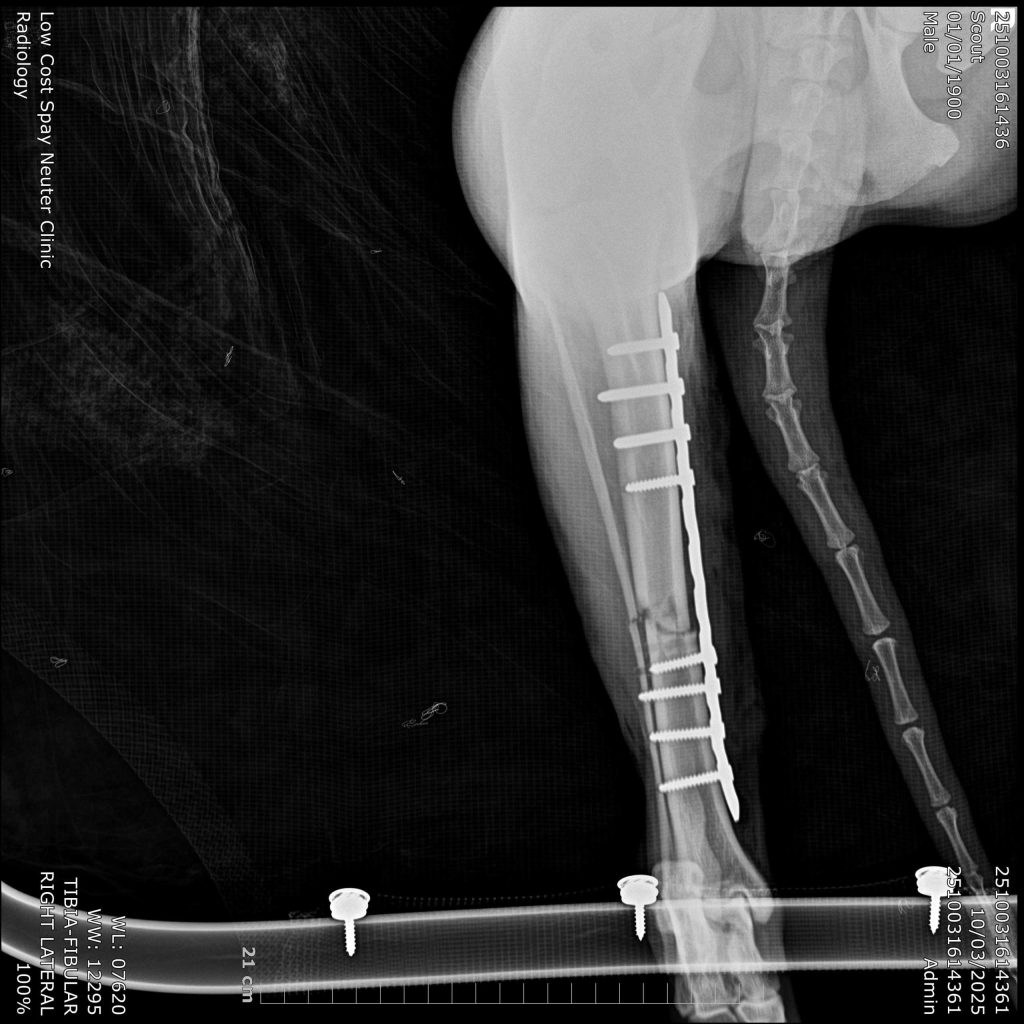

Fracture repair in cats and dogs typically involves surgical stabilization of the broken bone fragments to promote healing. Depending on the fracture type, location, age and body weight various techniques may be used. Proper immobilization, pain management, and rehabilitation are crucial for a successful recovery.

Price starts at $2,000 and will be at the surgeon’s discretion based on findings from x-ray and dependent on surgery time